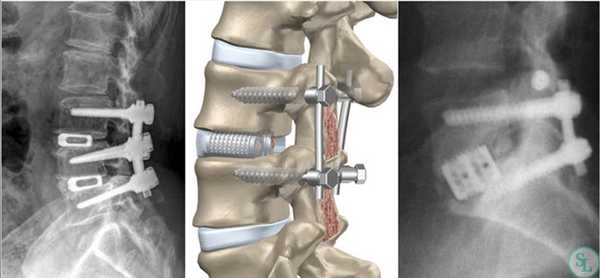

Транспедикулярная фиксация поясничного отдела позвоночника

Транспедикулярная фиксация позвоночника (далее ТПФ) является одной из самых распространенный операций в современной нейрохирургии.

По способу установки — ТПФ для «открытых» операций, когда осуществляется широкий доступ к структурам позвоночника и система устанавливается с использованием внешних анатомических ориентиров и дополнительного рентгенологического контроля, ПЕРКУТАННЫЕ ТПФ — системы, когда проводятся несколько маленьких разрезов в проекции введения винтов, сохраняется целостность многораздельных мышц, значительно снижается риск нагноения, кровопотери, связанной с доступом. Данная операция под рентгенологическим контролем, относится к минимально-инвазивной хирургии позвоночника (MIS).

Фиксация на 360 градусов

Фиксация на 270 градусов — использование только с одной стороны 2-х винтов (там, где проводилось удаление фасет-сустава и устанавливался межтеловой кейдж (т.н. TLIF)